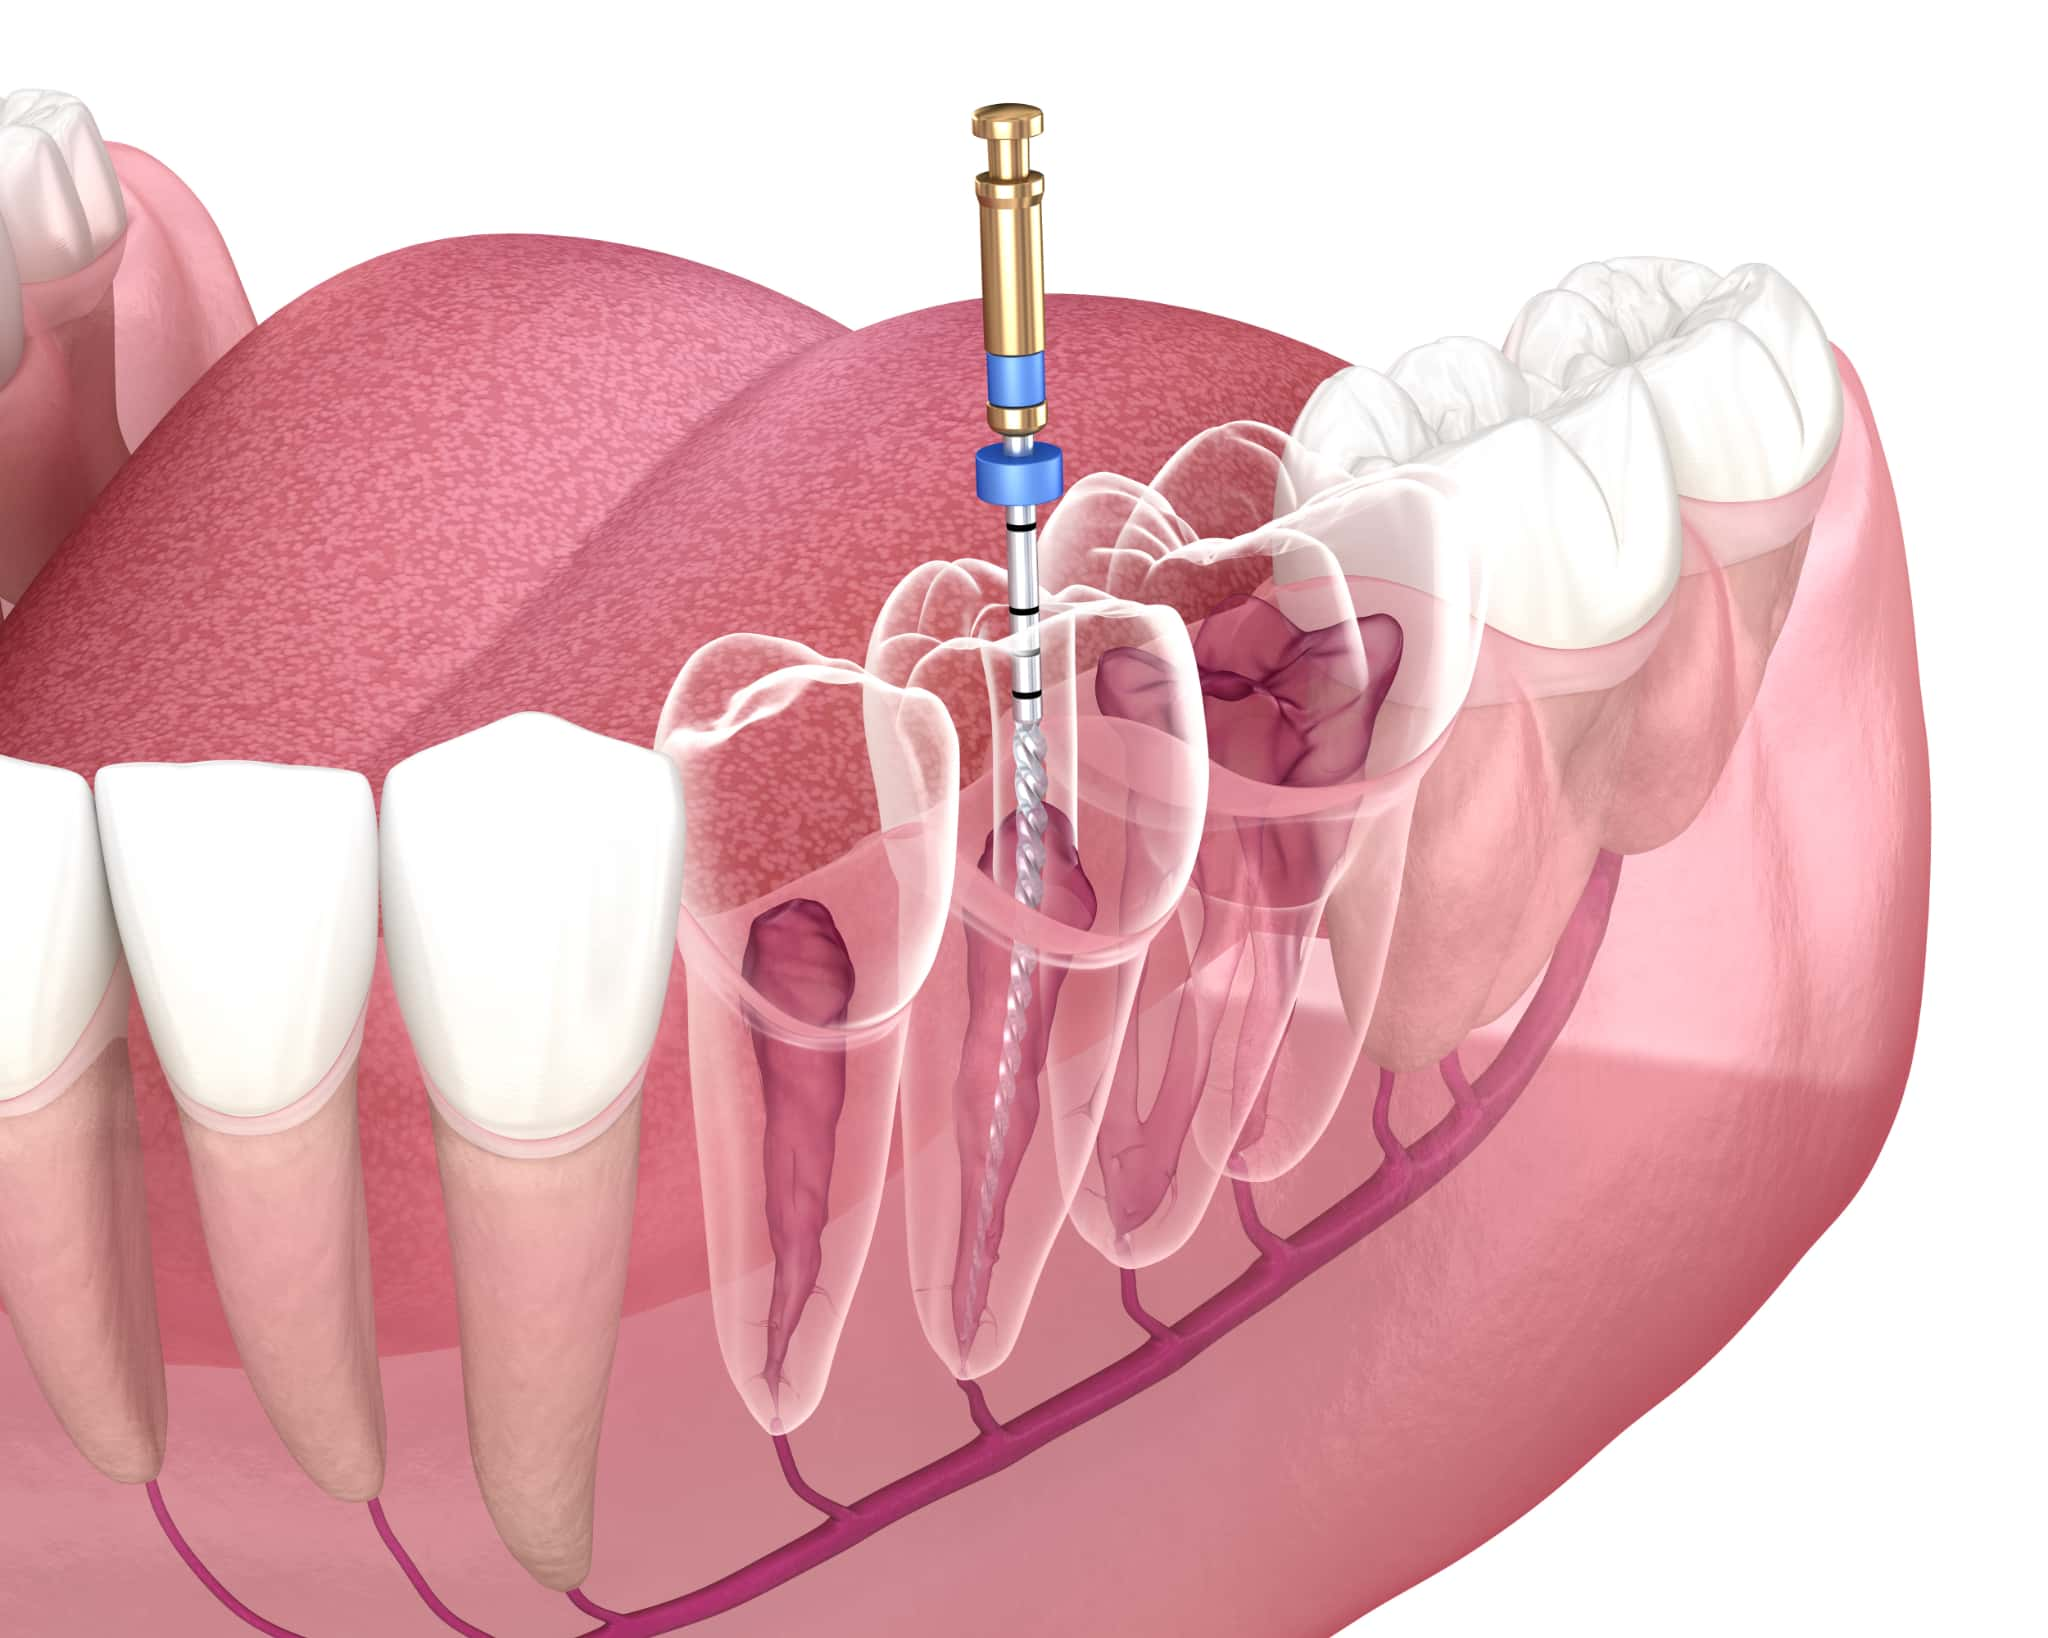

根管治療とは、歯の中にある根管と呼ばれる細い管の中から感染した組織を取り除いてきれいに洗浄・消毒し、隙間なく薬剤を詰めて密閉する治療法です。根管治療が必要になるのは、虫歯が歯の神経にまで達した場合や歯に強い痛みがある場合などです。

エナメル質と象牙質を超えて、歯の内部にある歯髄に細菌が侵入すると、強い痛みや膿が出るなどの症状が現れます。この状態で何もせずに放置すると、細菌がさらに広がって歯の根の先に炎症が起こって歯を支える骨を溶かしていきます。そのため、感染した根管内をきれいにして密閉する処置が必要になるのです。

感染している歯髄や組織を完全に取り除き、根管内をきれいに清掃・消毒します。根管は人によって形状や本数が異なり、曲がっていたり分岐していたりすることもあるため、専用の器具を使って丁寧に処置します。

根管内が複雑な場合は、CTなどの精密機器を活用した診断や、複数回に分けての治療が必要になることもあります。根管内が清潔な状態になるまで、洗浄を繰り返していきます。

薬剤の充填